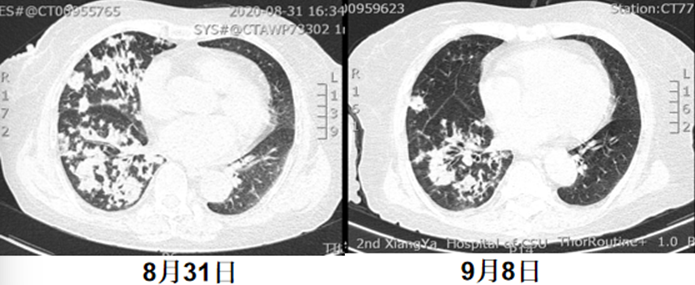

复查全腹部CT考虑不完全性肠梗阻及双肺感染,结合患者病史,考虑“外源性脂质性肺炎”可能性大。予以哌拉西林他唑巴坦抗感染,地塞米松抗炎,中药辅助治疗等;患者于8月20日左右出现发热,最高体温39.0℃,咳嗽咳痰症状较前加重,且伴有明显气促,无畏寒寒战,经治疗后仍有气促不适,为求进一步诊治,遂至我院门诊就诊,以“双肺病变查因”收住我科。起病以来,患者精神差,睡眠可,食欲减退,大便少,小便正常,体重未测。2020年8月13日于当地医院确诊为“不完全性肠梗阻、右肾囊肿”。余既往史无特殊。配偶2019年因肺结核去世。个人史、月经史、婚育史、家族史等均无特殊。体温36.5℃,脉搏82次/min,呼吸30次/min,血压100/57 mmHg。APACHE Ⅱ评分11分,SOFA评分2分,NRS-2002营养风险评分4分。急性面容,神清,精神较差,全身皮肤黏膜未见黄染,全身浅表淋巴结未触及肿大。胸廓无畸形,双侧呼吸动度对称,语颤无增强,双肺叩诊清音,双肺呼吸音粗,双肺可闻及干啰音,未闻及胸膜摩擦音。心率82次/min,律齐,各瓣膜听诊区未闻及病理性杂音。腹软,全腹无压痛及反跳痛,未触及腹部包块,肝、脾肋缘下未触及,腹部移动性浊音阴性,双肾区无叩击痛。肠鸣音正常。无杵状指(趾),双下肢不肿。2020年8月31日我院胸部CT示右肺弥漫性实变为主,伴渗出,左下肺亦有少许渗出(图3)。①双肺病变查因:外源性脂质性肺炎?Ⅰ型呼吸衰竭;②不完全性肠梗阻;③低蛋白血症;④低钠血症;⑤右肾囊肿。- 血气分析:pH 7.501,PaCO2 31.7 mmHg,PaO2 48.3 mmHg,Lac 0.9 mmol/L,HCO3- 25.9 mmol/L。